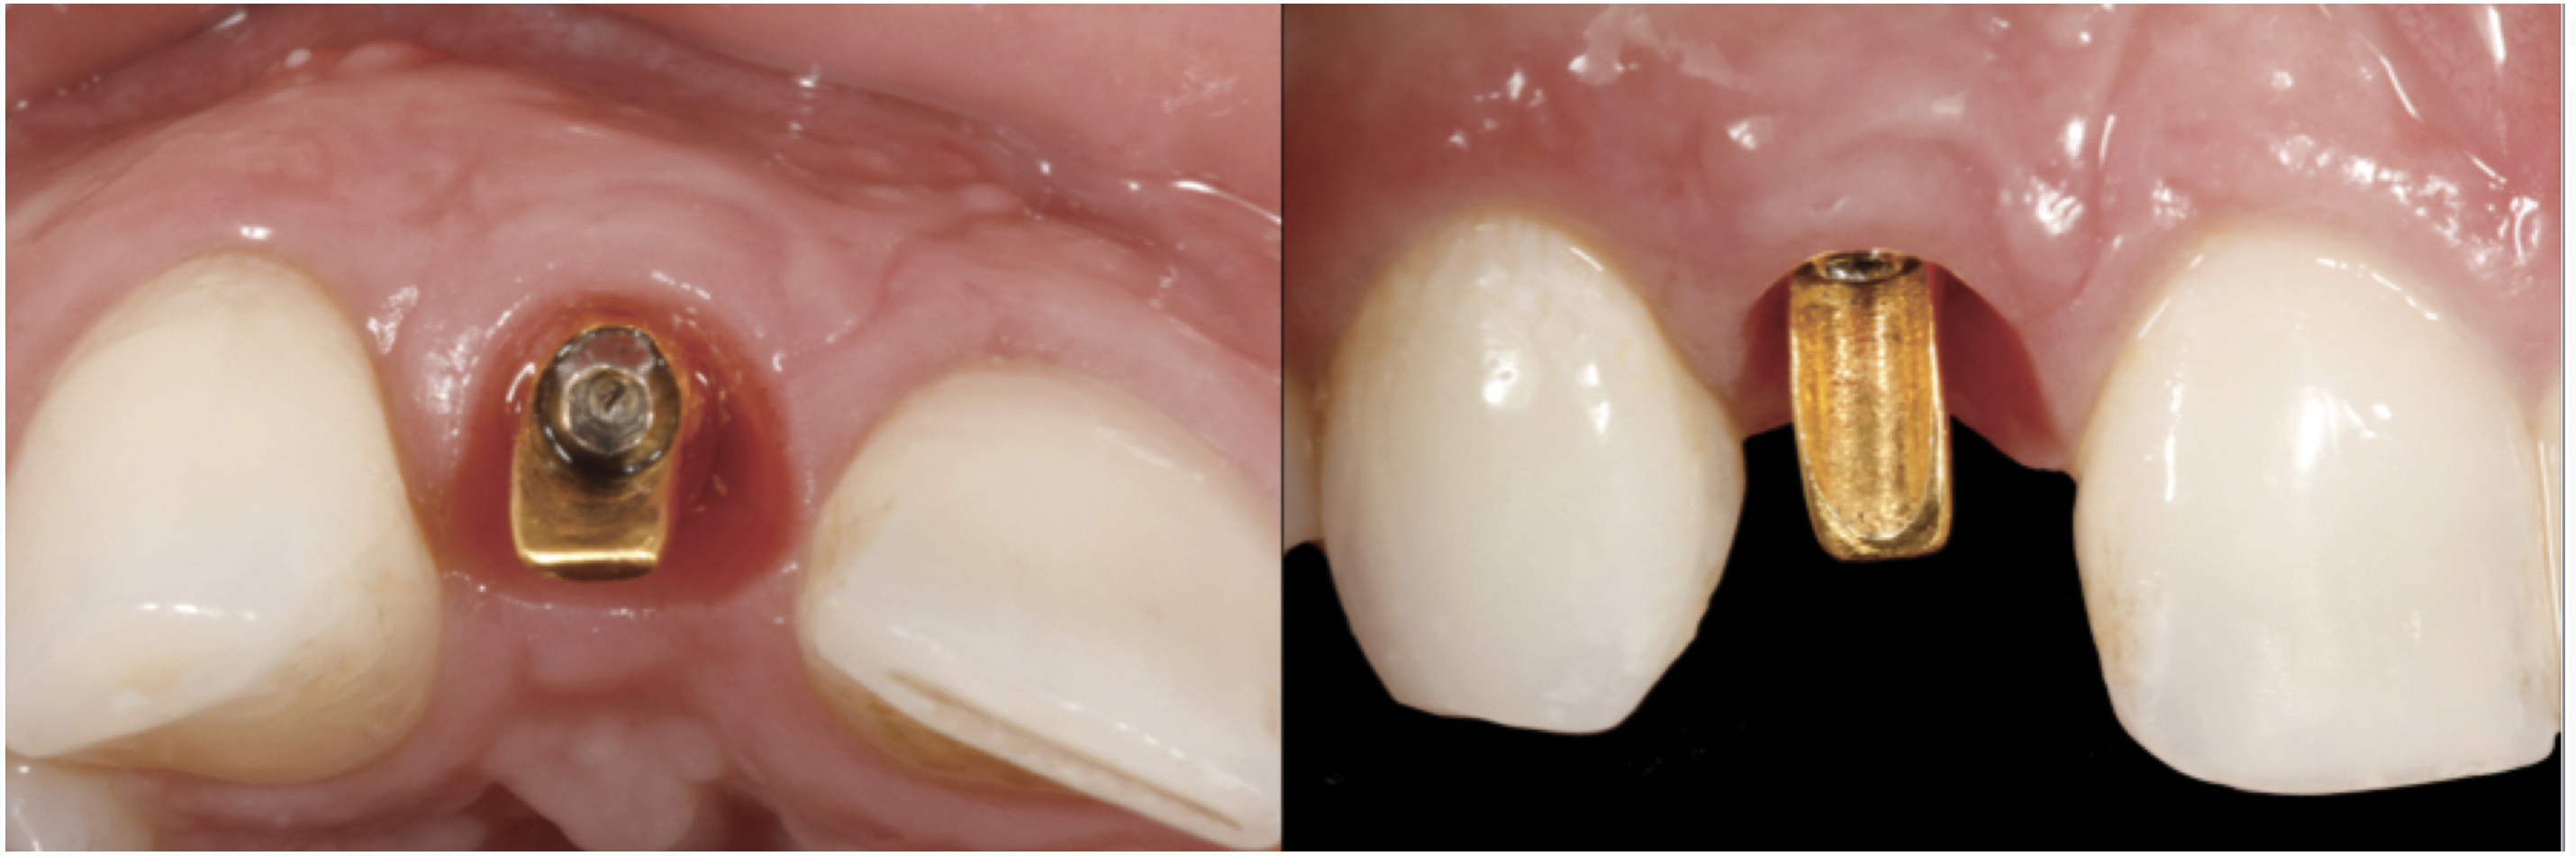

Fig 44. A new metal-alloy abutment was fabricated for the narrow-diameter implant with a cement-retained metal-ceramic crown.

Figure 44

Fig 45. The definitive crown tooth No. 26 seated in place and provisionally cemented. The recession defect was eliminated with the removal and replacement of a new implant in the proper position.

Figure 45

The crown and screw-retained custom abutment were removed, and a surgical cover screw was placed into the implant, thereby allowing spontaneous gingival augmentation in situ (Figure 33 and Figure 34). Note that the lingual aspect of the implant site was significantly more coronal than the labial aspect, which was positive because the defect would be limited to a facial–lingual defect. A fixed RBR bridge was cemented on the adjacent teeth and used as a tooth-supported transitional provisional restoration (Figure 35). A few weeks were allotted to let the soft tissue heal and migrate around the cover screw (Figure 36) to see if there would be complete coverage, thereby allowing a soft-tissue augmentation procedure to be performed with primary flap closure as in clinical scenario No. 2. The major obstacle in achieving a positive tissue response was that the implant depth was also deficient because the implant–abutment connection was at the level of the free gingival margin. It was decided that the best treatment option would be to remove the implant. A high-powered reverse-torque device (Fixture Remover Kit, NeoBiotech, www.neobiotechus.com) was used to remove the implant atraumatically (Figure 38 through Figure 41). The implant socket was allowed to heal for several months not unlike an extracted tooth (Figure 42). A new implant was placed in a better position from both a restorative and esthetic perspective (Figure 43), and after a few months of healing, a new crown was made (Figure 44). A satisfactory functional and esthetic result was achieved (Figure 45 and Figure 46) without employing pink porcelain.